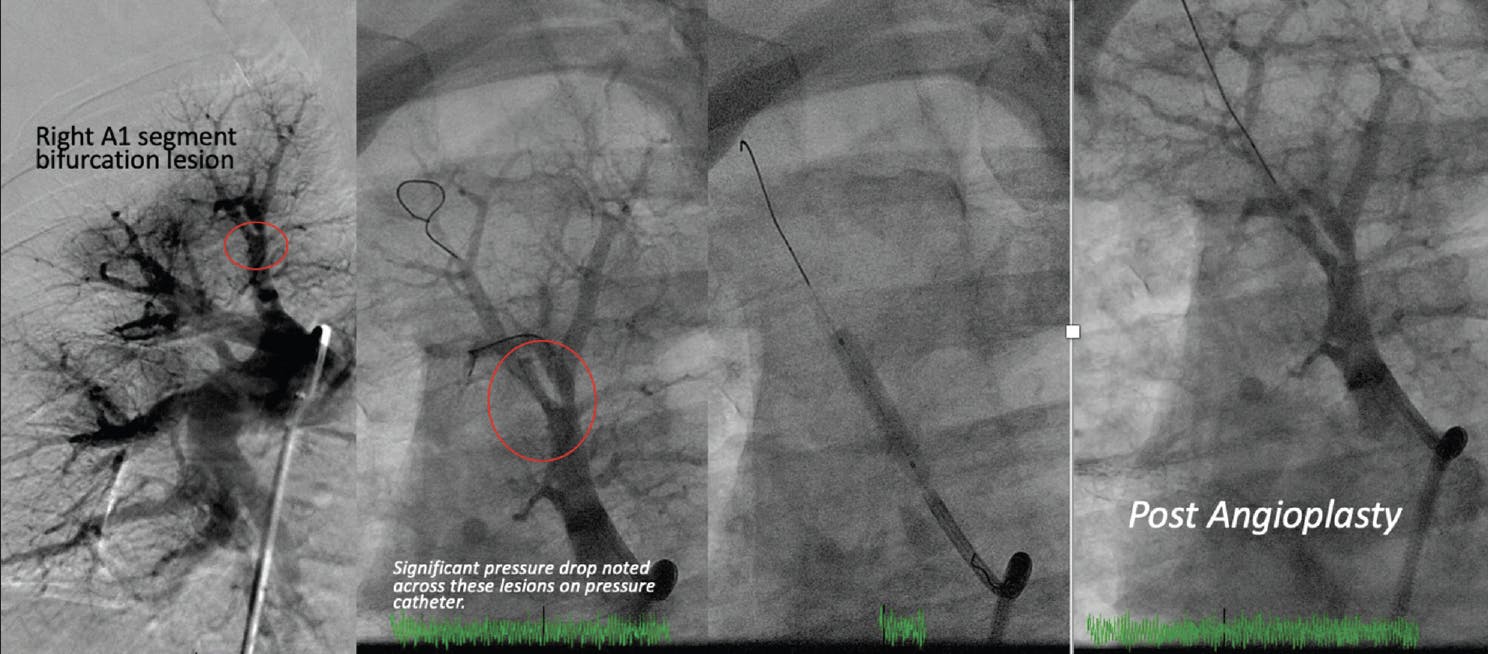

This session focused on the successful treatment of right upper lobe segments A1 and A3. Cannulation utilized an MPA-2 guide catheter with a telescoping guide extension catheter. Presence of ring-like stenosis at the bifurcation of the RA1 and RA3 segmental branches prompted sequential dilation with a buddy wire in place (Figure 4).

Figure 4. Successful BPA of the right upper lobe A1 segments.